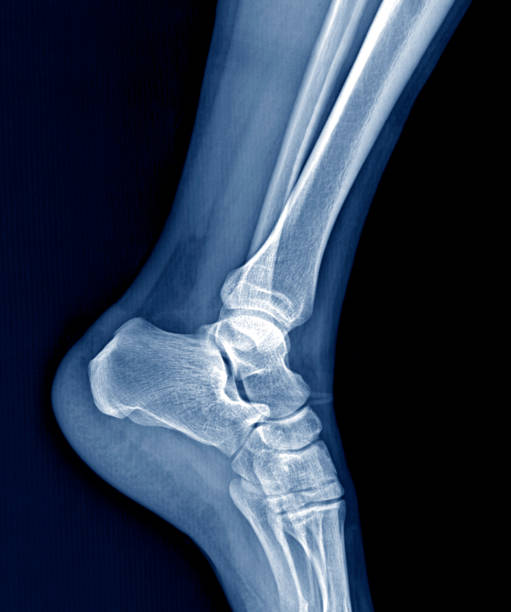

발뒤꿈치가 아픈 이유 첫 번째는 족저근막염입니다. 족저근막은 발뒤꿈치 뼈에서 시작하여 발바닥 앞쪽으로 연결되는 두껍고 강한 섬유질 띠입니다. 족저근막은 우리 몸의 중요한 역할을 하는데 아치 모양의 모양새는 우리 몸의 체중을 흡수하기 때문에 걷는 데 중요한 역할을 할 수 있습니다. 족저근막염은 이러한 족저근막에 반복되는 충격으로 근막을 둘러싸고 있는 콜라겐이 변성하면서 염증이 생긴 것을 의미합니다.

이러한 증상은 원래부터 평발이거나 걸음걸이나 생활습관 등으로 발이 변형되며 구조적으로 이상이 생겨서 문제가 생길 수도 있지만 기본적으로 하체 사용을 무리하게 하다보면 문제가 생기게 됩니다. 족저근막염 통증은 개인에 따라 다르지만 기본적으로 발뒤꿈치에 통증을 느끼게 되고 특히 아침 기상후 첫 걸음부터 통증이 나기 때문에 조기에 치료를 받는 것이 중요합니다.

발뒤꿈치가 아픈 이유 2. 아킬레스건염

발뒤꿈치가 아픈 이유 두 번째는 아킬레스건염입니다. 아킬레스건염은 아킬레스건 부위가 반복적으로 미세한 손상을 입으면서 생기는 통증으로 이 역시 발뒤꿈치 통증을 유발합니다.

아킬레스건염 역시 뒤꿈치 혹은 발바닥에서 주로 통증이 느껴지며 특히 아킬레스건 부위가 부어오르며 움직임을 가져간 이후에는 종아리에서부터 발뒤꿈치까지 통증이 심하게 나타나고 이러한 증상이 지속되면 무플, 고관절, 허리에까지 무리가 갈 수 있기 때문에 족저근막염과 마찬가지로 빠른 치료를 받는 것이 중요합니다.